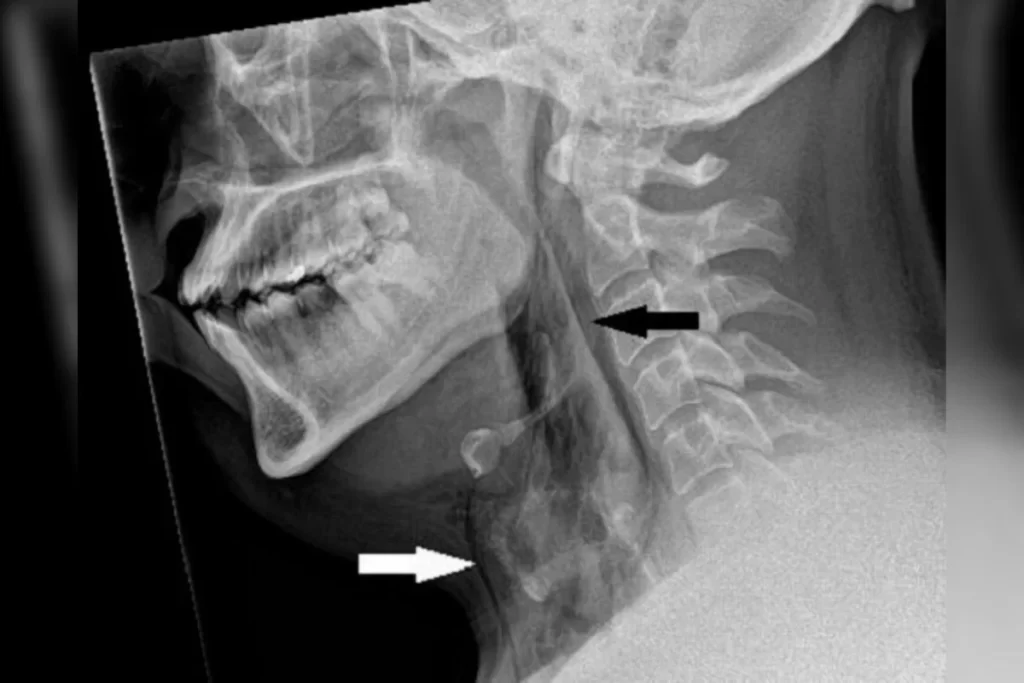

Sentindo fortes dores no peito, o paciente se dirigiu ao hospital para atendimento de emergência. A ruptura na traqueia foi revelada por exames de imagem e tinha uma área de cerca de quatro milímetros quadrados.

“É raro, mas o acúmulo rápido de pressão na traqueia ao espirrar com o nariz apertado e a boca fechada ocasionou um rasgo traqueal, conforme os exames realizados no hospital de Dundee mostram”,

destaca o texto da equipe médica.